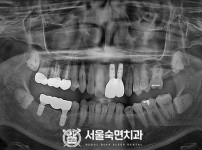

임플란트-전후사진1